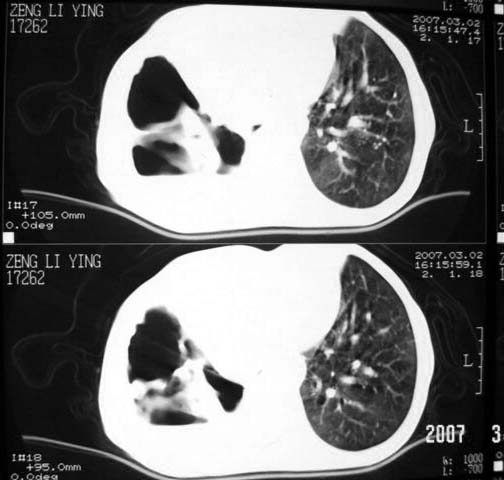

以下是引用dyqct在2007-3-2 22:04:00的发言:[br]考虑:1、右侧毁损肺伴支气管胸膜瘘(多条支气管与胸腔相通、液气胸);[br] 2、左肺浸润型肺结核。[br][br][br][br]